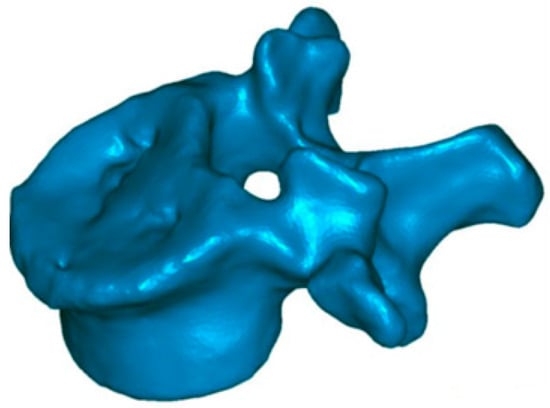

3.1. Case 1

In this case, the patient was discharged from hospital three days after surgery. He went back to work three months after surgery, with a reduction of pain around 64% (level 8 in preoperative with VAS, until 2.9 at hospital discharge). The procedure was developed without problems, except for a minor non-symptomatic leakage in the intervertebral disc. The traumatic kyphosis vertebral angle was reduced a 62% in the sagittal plane (from 9.7° preoperative to 3.7° at discharge). 3D reconstructions (Figure 6) show that the defects in the superior endplate were corrected (Figure 6). The 3D mapping allowed for a precise quantification of this restoration for the whole vertebral body, and especially for both endplates (Figure 7) as well as the cortical ring restoration evidenced on the X-ray examination. The procedure has allowed to restore the endplate defect increasing the superior 6–2.5 mm of height increase in 85% of the total surface of the superior endplate.

Figure 6.

Superior endplate reduction. Preoperative reconstruction.

Figure 7.

Topogram showing the 3D reduction of the vertebra superior endplate. The colour scale represents the reduction with red being the maximum and white the minimum (0–8 mm).

The patient’s follow-up at 3, 6, and 12 months showed the efficacy of the treatment. At 3 and 6 months, the pain (VAS scale) was reduced to 2, and to 1.5 at 12 months. With respect to the vertebral height maintenance angle, we have observed 3.7° at 3 months, 3.6° at 6 months, and 3.8° at 12 months.